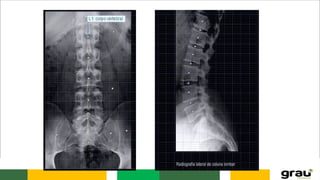

Coluna Vertebral

CURVATURAS: Primárias e secundarias

IMPORTÂNCIA CLINICA: hipercifose, hiperlordose escoliose

IMAGEM PANORÂMICA DA COLUNA !

COLUNA VERTEBRAL CURVATURAS: Primáriase secundarias IMPORTÂNCIA CLINICA: hipercifose, hiperlordose escoliose Caracteristicas das vértebras permitem identificar a que região pertencem.